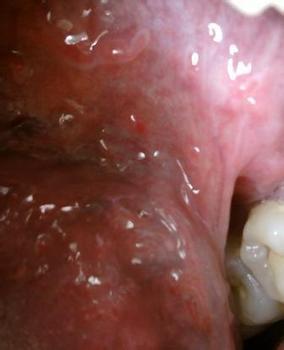

尖锐湿疣的症状

疱疹以及湿疣是性病种类中比较常见的两种,而且疱疹有生殖器带状等分类,湿疣也有假性尖锐湿疣分类。不同的发病分型治疗的方法以及药物的选择都与治疗效果有重要的影响,很多患者在性病发病之后不知道怎么治疗,那么,治疗疱疹和湿疣需要患者们早期治疗最佳。

我院专业治疗尖锐湿疣和疱疹专家指出,治疗疱疹和湿疣用什么药好?用药选择直接关系治疗效果。现在性病治疗医院有很多,药物种类也有很多。治疗尖锐湿疣的药物都有较强的腐蚀作用,会对人体皮肤产生损害,有的还会引起人体的过敏反应。此外,药物只能针对尖锐湿疣的表面疣体进行清除,不能彻底杀死人体内的湿疣病毒,治愈后尖锐湿疣还是会复发,不能根治。